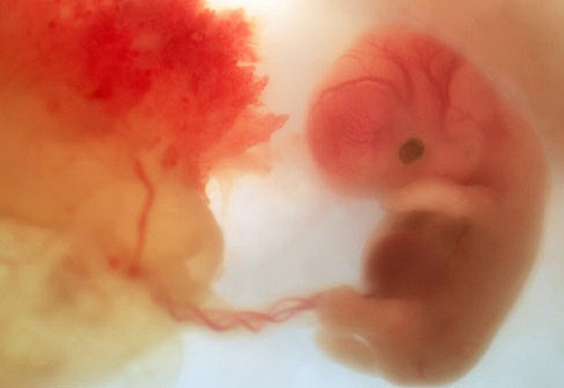

En la 6 semana del embarazo ocurren cambios.El embrión ya mide entre 2 y 4 milímetros en la 6 semana de embarazo. Este es el comienzo del periodo embrionario, se produce la formación de la mayoría de los órganos y en este momento es que se forman las malformaciones

En esta semana a la mujer le ocurren cambios y también ya se a desarrollado un poco el feto en la séptima semana de gestación. El embrión tiene 5 semanas de vida y mide aproximadamente 1,3 centímetros. La mujer puedes sentir frecuentemente deseos de orinar. Es normal porque el útero empieza a ejercer presión sobre la vejiga.

El embrión mide aproximadamente 13 mm desde la punta de la cabeza hasta las nalgas.Comienza en su cabeza a formarse y perfilarse las orejas , los ojos y donde empieza a formarse la punta de la nariz, la cabeza es todavía muy grande en comparación con el resto del cuerpo. Por eso, aunque su columna vaya enderezándose poco a poco, la cabeza todavía permanece hacia delante. También comienza a borrarse la columna del embrión y comienza a formarse los cuatro huesos unidos los cuales forman el coxis.

En la 9 semana del embarazo tu bebé,que en este momento se conoce como feto, ahora que la cola del embrión ha desaparecido,en esta semana ya comienza a estirarse y enderezar su tronco y este bebe mide cerca de 2,5cm de largo.